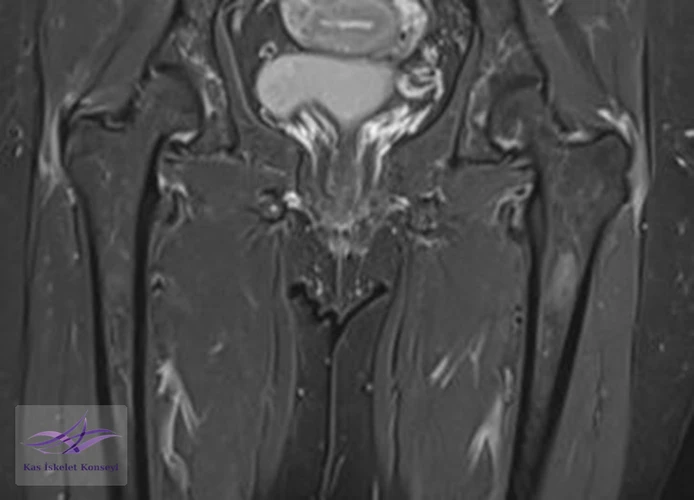

İncelemeler: Lomber MRG: L4-5 diskal bulging ve sol foraminal stenoz var. Kalça MRG istendi, iki yanlı trokanterik bursit rapor edildi.

Resim 4. Kalça MRG koronal kesit, solda hakim iki yanlı trokanterik bursit ile uyumlu.

Tedavi için öncelikle trokanterik bursa enjeksiyonları öngörüldü. Bu tedaviden alınacak yanıt görüldükten sonra mevcut lomber patolojisinin (foraminal stenoz) tekrar değerlendirilmesi önerildi. İki yanlı belirgin trokanterik bursit görülmesi nedeniyle polimyalgia romatika açısından da incelenmesi önerildi.